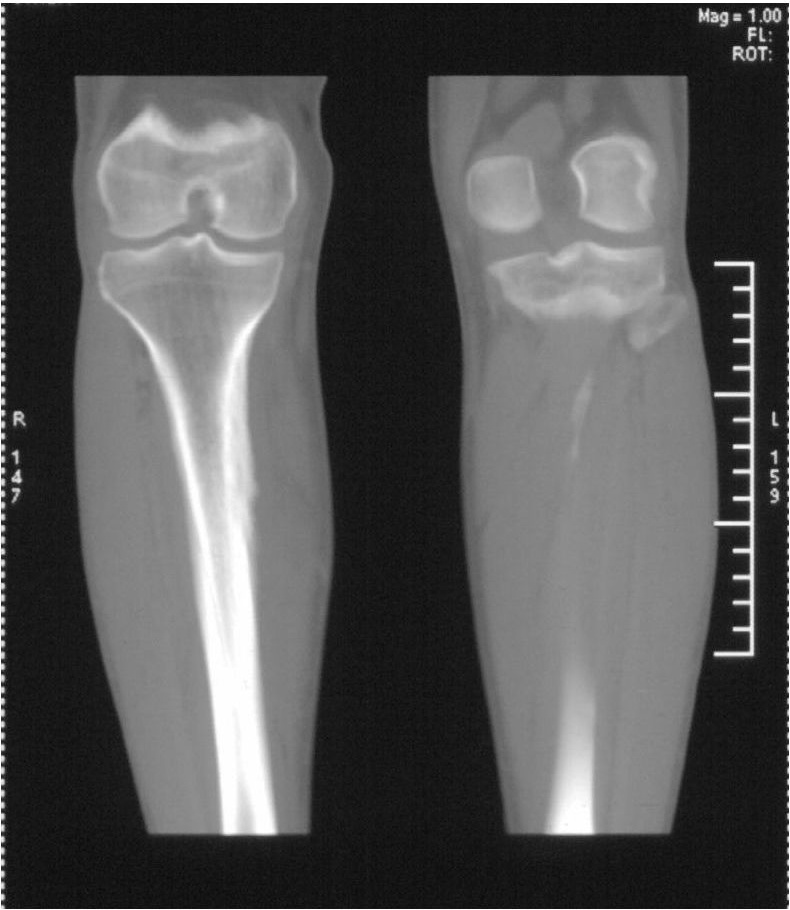

男,42岁。4个月前钢筋钝伤右侧小腿部,当时因无明显外伤,未引起重视。一周后因受伤腿部疼痛,发现肿胀,随后到当地医院进行检查(2008年4月16日)。因未发现骨质异常未引起重视,仅仅进行口服抗生素治疗处理。经过一段时间治疗但未见明显治疗效果在5月29日又进行x线检查,发现有胫骨密度上段密度增高,又进行抗炎治疗,仍未见效果。又在7月3日进行x线检查,仍然报告有胫骨上端密度增高,并建议ct检查。以下是相关检查结果:

髓腔密度呈絮状增高,胫骨上端内侧可见层状骨膜反应,考虑骨髓炎.

髓腔密度呈絮状增高,胫骨上端内侧可见层状骨膜反应,肌间隙模糊,考虑骨髓炎.

破坏、增生、骨膜反应,考虑骨髓炎